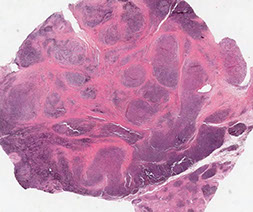

Micro: infiltrating nodules (cannon-balls) and sheets of compact spindle cells c slit-like lumina

- platelets get stuck in whorled nodular vascular channels

- has dilated lymphatic channels at periphery

IHC: (+) VEGFR-3

- GLUT-1 negative (unlike infantile hemangioma)